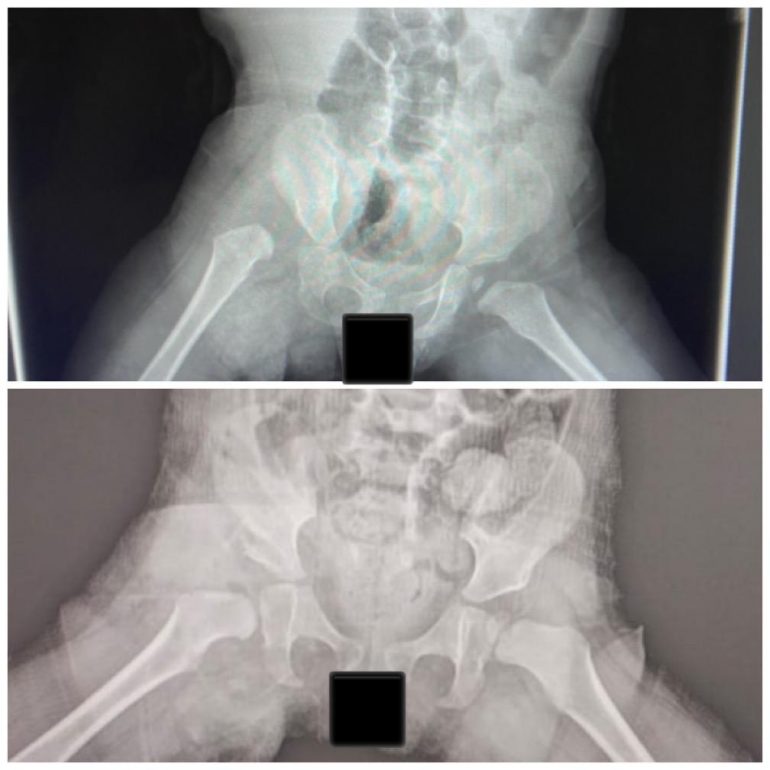

وأوضح تجمع الرياض الصحي الثالث أن الطفلة كانت تعاني بسبب عرجة شديدة نتيجة خلع مفصل الورك، الذي بدوره سبب لها معاناة في المشي، وكان سيتسبب مستقبلاً في حال عدم علاجه في آلام مزمنة وخشونة مبكرة، واصفًا تلك الحالة بأنها معقدة؛ لأنه لم تجرَ لها عملية إعادة الخلع بوقت مبكر.

وأضاف بأنه تم من خلال فريق طبي، يشرف عليه استشاريو جراحة عظام الاطفال، إجراء الفحوص والأشعات اللازمة، وتهيئة متطلبات عملية التدخل الجراحي لإعادة خلع الورك لدى الطفلة، وتم ذلك بالشكل المطلوب. وقد استمرت العملية ساعتين، تم خلالها إرجاع مفتوح لمفصل الورك، مع قص عظمة الحوض لتحسين التغطية وتثبيتهما، مع تحرير الأنسجة حول المفصل، ووضعها في جبس بنطلوني لمدة ثلاثة أشهر.